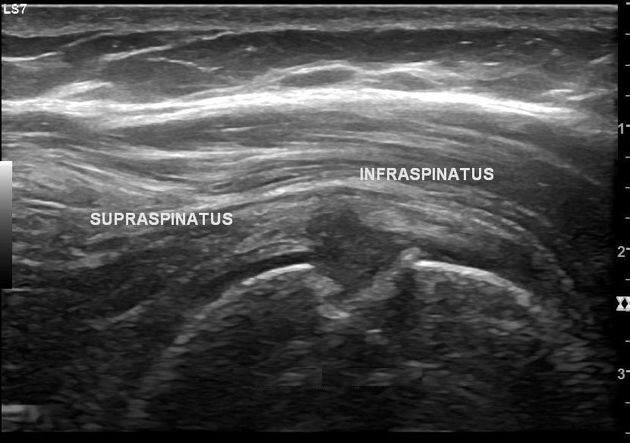

QUAL A ESTRUTURA ASSINALADA NA IMAGEM OBTIDA EM UMA ULTRASSONOGRAFIA DE OMBRO?

PORÇÃO EXTRA ARTICULAR DO TENDÃO DA CABEÇA LONGA DO BÍCEPS BRAQUIAL

QUAL A ESTRUTURA ASSINALADA NA FIGURA?

TENDÃO DO SUBESCAPULAR (CORTE LONGITUDINAL)

TENDÃO DO INFRAESPINHAL

TENDÃO DO SUPRAESPINHAL